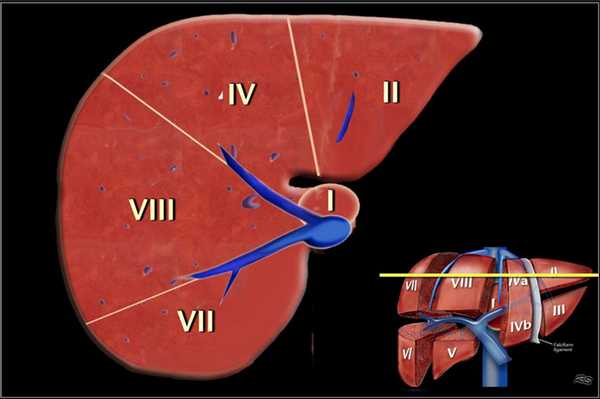

Классификации Couinaud.

По классификации Couinaud печень делится на восемь независимых сегментов. Каждый сегмент имеет свой собственный сосудистых приток, отток и желчный проток. В центре каждого сегмента есть ветви воротной вены, печеночной артерии и желчного протока. На периферии каждого сегмента вены, собирающиеся в печеночную вену.

- Правая печеночная вена делит правую долю печени на передний и задний сегмент.

- Средняя печеночная вена делит печень на правую и левую доли. Эта плоскость проходит от нижней полой вены до ямки желчного пузыря.

- Серповидный связка отделяет левую долю с медиальной стороны — сегмент IV и с латеральной сторон — сегмент, II и III.

- Воротная вена делит печень на верхние и нижние сегменты. Левая и правая воротная вена делится на верхние и нижние ветви, устремляясь в центр каждого сегмента. Изображение представлено ниже.

На рисунке изображено печеночные сегменты, фронтальный вид.

- На нормальной фронтальной проекции VI и VII сегментов не видно, поскольку они расположены более кзади.

- Правая граница печени формируется из сегментов V и VIII.

- Хотя сегмент IV является часть левой доли, он расположен правее.

Couinaud решил разделить печень в функциональном плане на левую и правую печень по проекции средней печеночной вены (линия Кэнтли).

Линия Кэнтли проходит от середины ямки желчного пузыря кпереди до нижней полой вены кзади. Изображение представлено ниже.